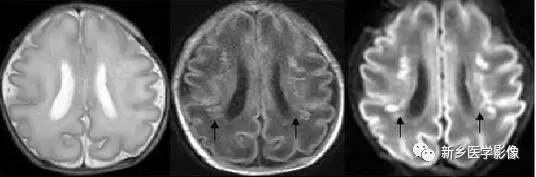

(2)脑裂畸形:胚胎期脑的发育经历6个主要阶段:①背侧诱导阶段;③腹侧诱导阶段;③神经增生阶段;④神经元移行阶段;⑤组织形成阶段;⑥髓鞘形成阶段。脑裂畸形发生在神经元移行阶段。脑裂畸形可累及一侧或双侧大脑半球,脑裂畸形位于侧面.常累及中央前、后回区偶尔位于大脑半球的其他部位。脑裂畸形的裂隙可以很窄,裂隙两侧灰质紧密相贴,称闭合型。裂隙也可以很宽,中间为脑脊液,分离型。

分离型脑裂畸形需要与脑穿通畸形囊肿鉴别.脑裂畸形的裂隙两旁一定为一灰质结构,而脑穿通畸形囊肿周围无脑灰质包绕。裂隙两旁是否为灰质结构是区别脑裂畸形与脑穿通畸形囊肿的可靠征象。裂隙两侧的灰质可不正常,可呈多小脑回样。脑裂畸形也可合并脑灰质异位。

分离型在CT很容易显示.闭合型有时容易漏诊.MRI对裂隙两侧的灰质结构容易辨认。脑裂畸形常合并透明隔缺如.侧脑室扩大,脑裂畸形处脑室边缘不规则.常可见指向裂隙的裂或 三角形憩室存在。

临床上脑裂畸形常表现有癫痫发作,其他神经系统症状可从很轻微到很严重.主要取决于脑裂畸形使脑组织缺损的严重程度。单侧闭合型脑裂畸形症状通常较轻,双侧分离型脑裂畸形症状较明显。